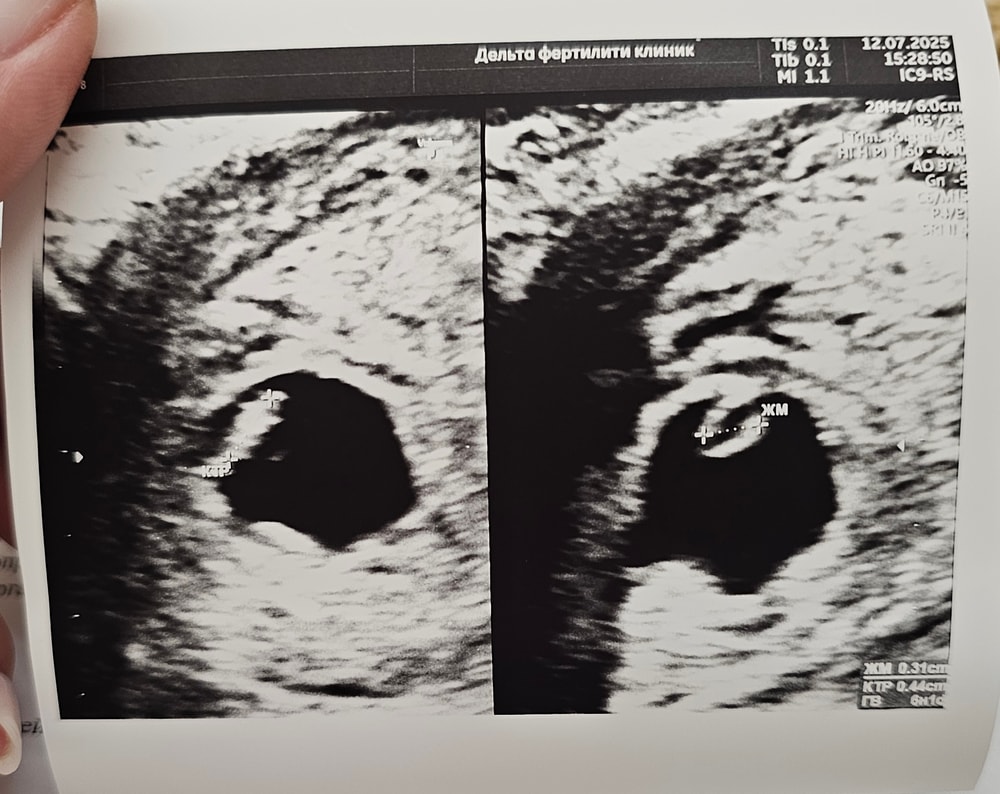

По узи все хорошо. КТР 4,4 мм, ЖМ 3,1. Срок поставила акушерский 6+1 по ктр. 2 дня назад на узи в жк поставили 6+3, но по плодному. У всех такие разные подходы 🥲 И какой, блин, срок верный?)

Сердцебиение чётко определяется, показали креветку, записала мужу на видео пульсацию.